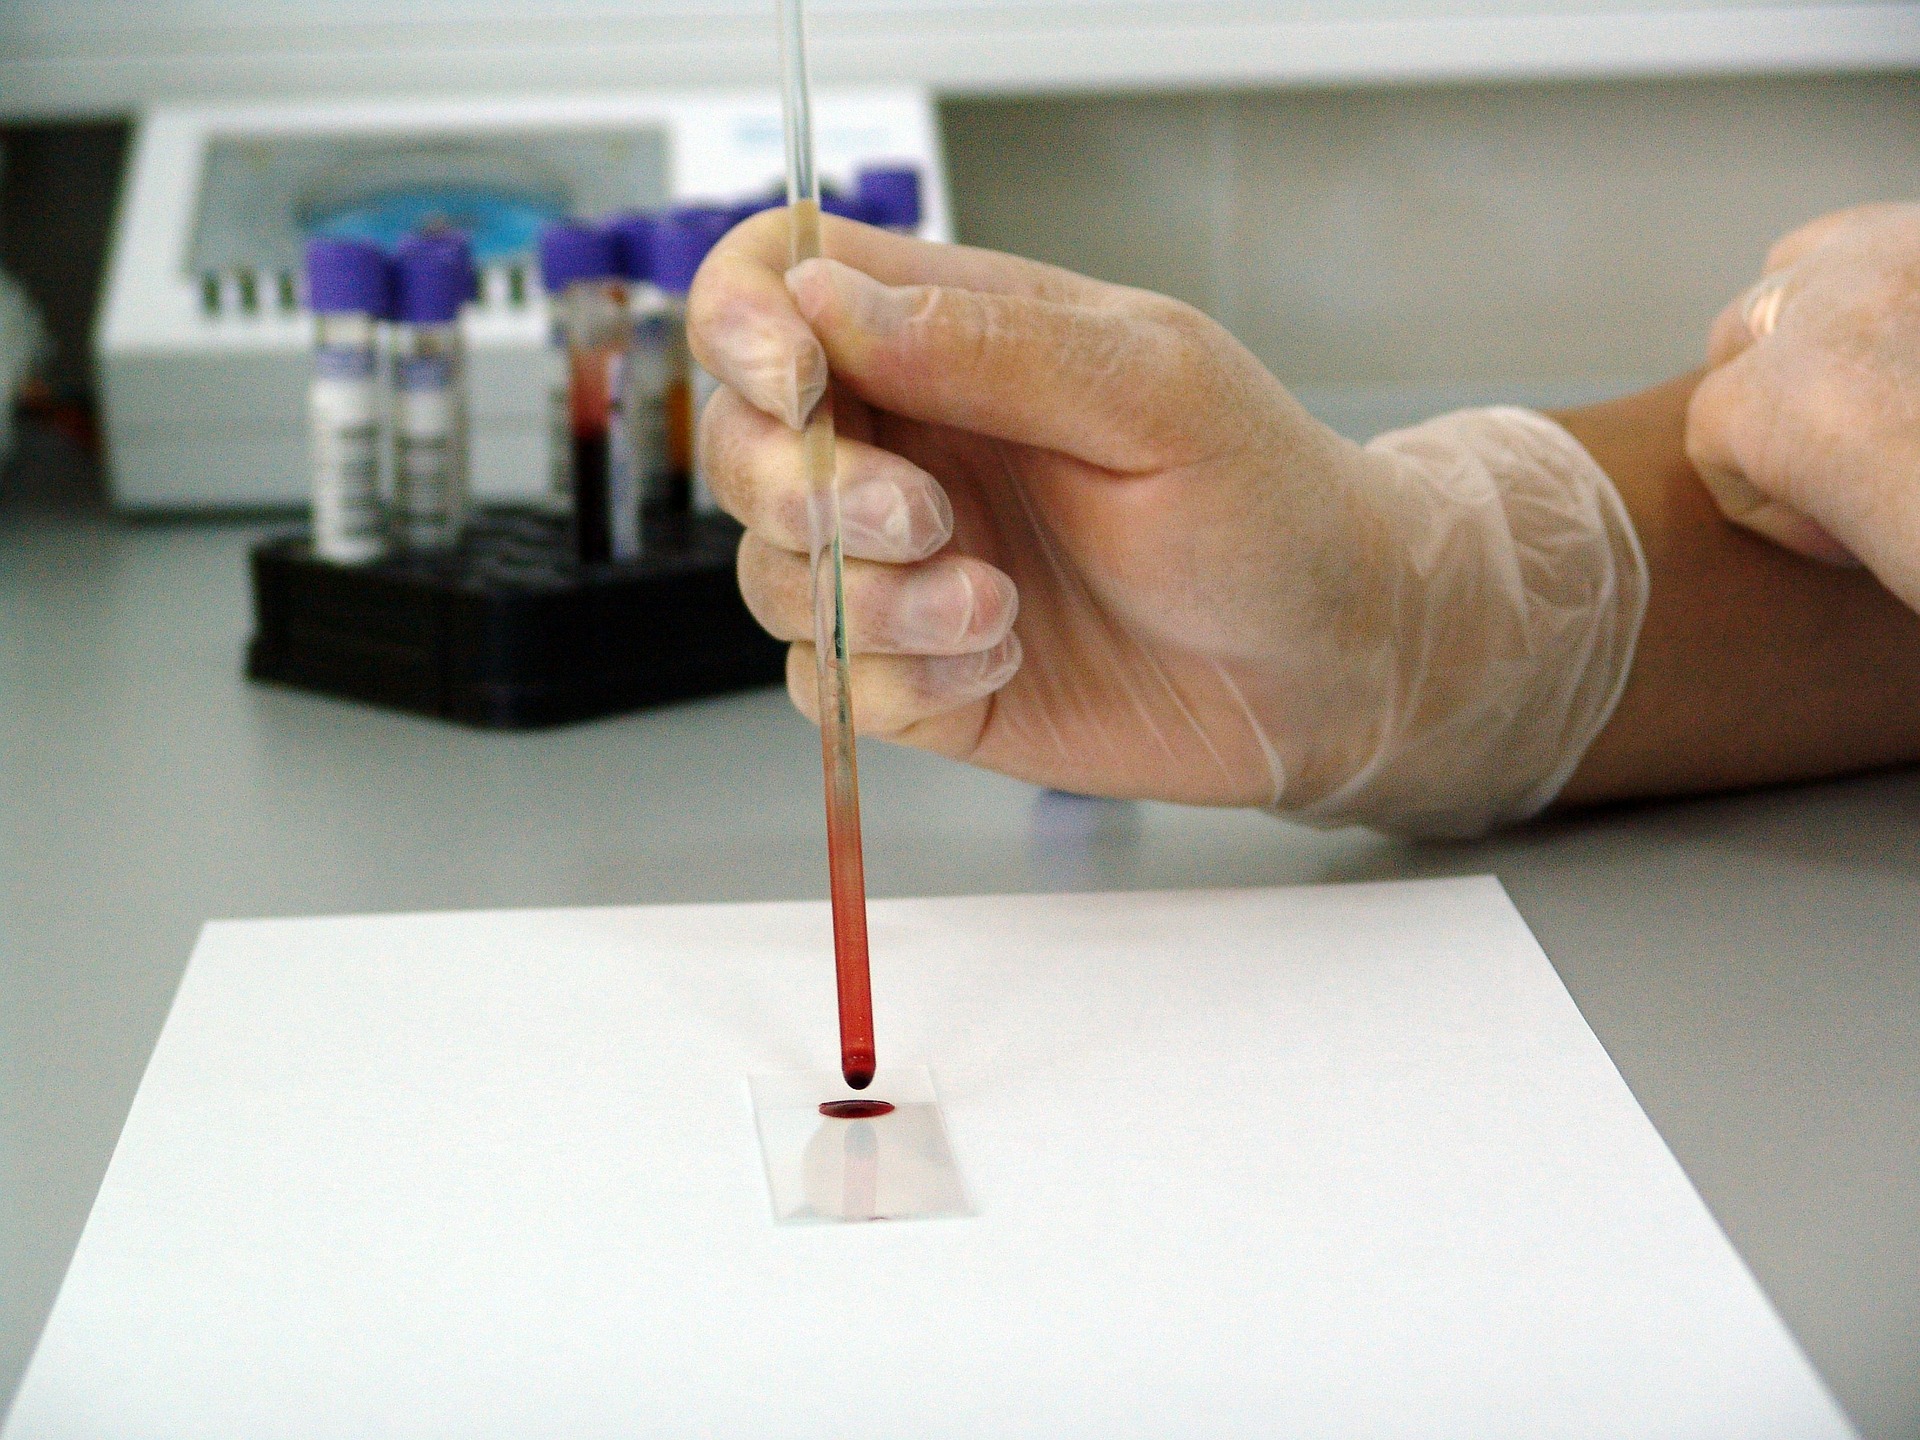

New Blood Test For Lung Cancer Can Detect Signs Five Years Before Chest Scans

A new breakthrough blood test will be able to show signs of lung cancer five years before chest scans can show any damage. This would enable patients to start treatment much earlier, thus greatly boosting their chances for survival. The blood test works by looking for “defender” cells. “Defender” cells are antibodies that are created…

New Cheap Blood Test For Lung Cancer

A new blood test for lung cancer has been developed which can produce results within five hours and is also 600 times cheaper than other methods. Usually, a test for lung cancer would involve a biopsy of lung tissue along with DNA sequencing. This process can take up to three weeks to produce results and…